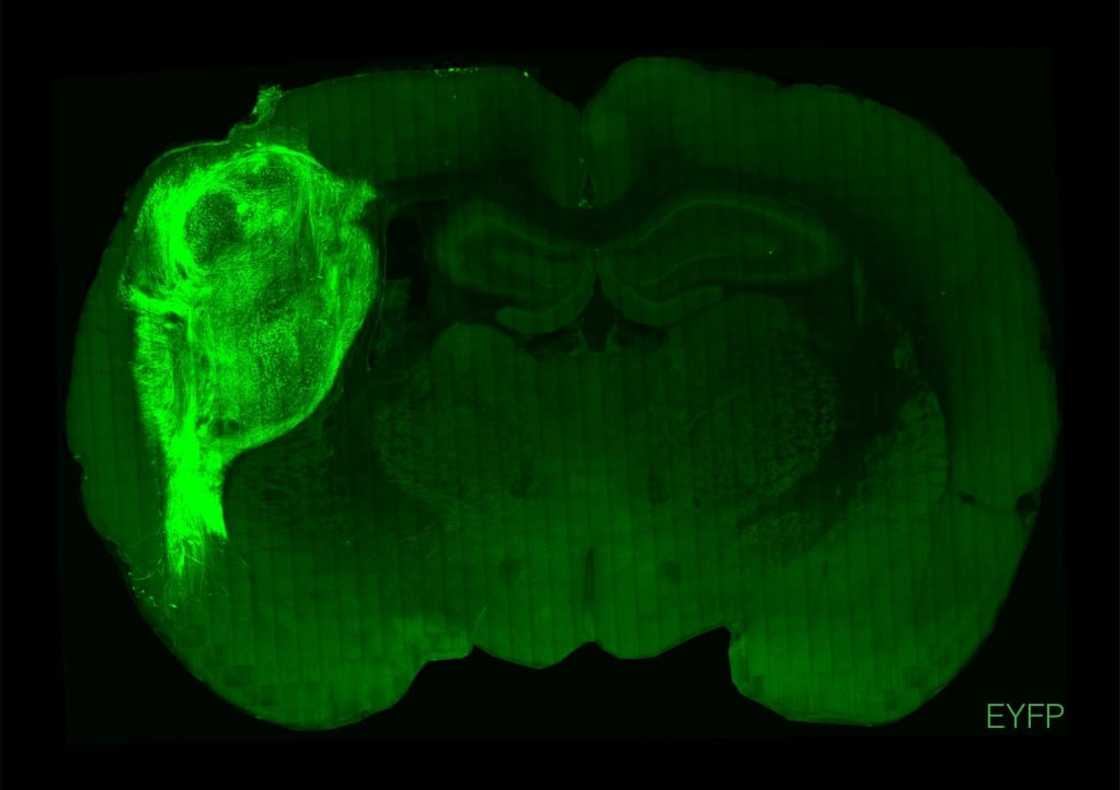

"By transplanting them at these early stages, we found that these organoids can grow relatively large, they become vascularised (receive nutrients) by the rat, and they can cover about a third of a rat's (brain) hemisphere," Pasca said.

To overcome those limitations, researchers implanted the groupings of human brain cells, called organoids, into the brains of young rats.

To test how well the human neurons integrated with the rat brains and bodies, air was puffed across the animals' whiskers, which prompted electrical activity in the human neurons.

That showed an input connection -- external stimulation of the rat's body was processed by the human tissue in the brain.